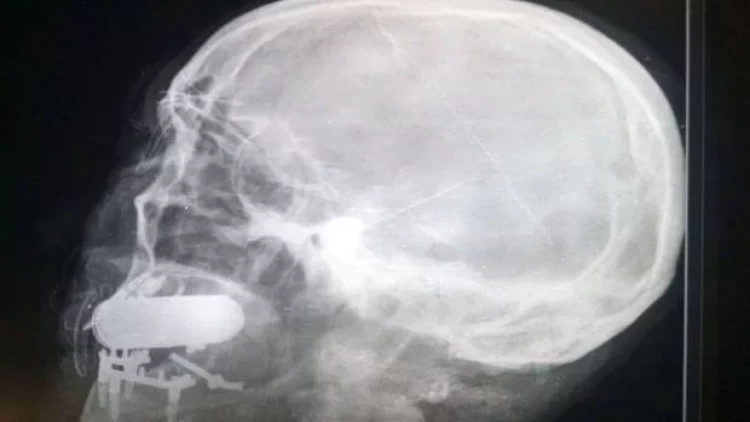

Müdaxilədən əvvəl döyüşçü rentgen müayinəsindən keçib. Görüntüdə mütəxəssislər yad cisim aşkar ediblər, lakin onun mənşəyi məlum olmayıb. Əşyanın döyüş sursatı olduğu təxmin edilir. Təhlükəsizlik üçün cərrah gülləkeçirməz jilet, taktiki eynək və dəbilqə taxıb.

Müdaxilə zamanı həkim düyməli detonatora bənzər hissəsi olan silindrin kənarını görüb. Həmin an mütəxəssis partlayış baş verərsə, heç kimin xəsarət almaması üçün həmkarlarını otağı tərk etməyə çağırıb və işini davam etdirib.